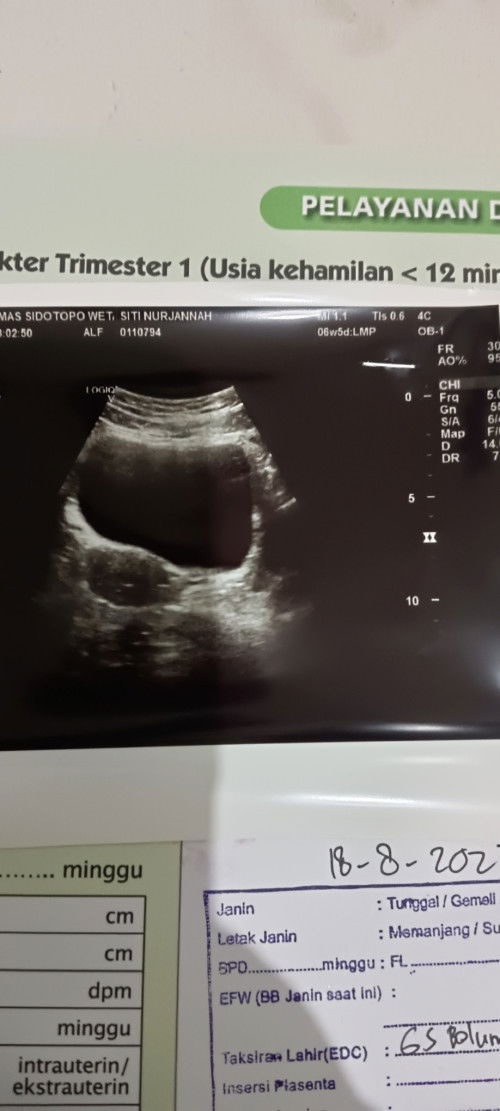

saya usia hamil kalau sesuai hpht udah 9minggu dan kmaren usg katanya, ada kista nya kecil dan kata dokter ada kemungkinan nanti hilang sndiri dan nanti nunggu d pantau lagi sampai bulan depan apa dsini juga ada yg pernah ngalamin seperti itu? soalnya ini pengalaman pertama saya d kasih tau ada kista pas lagi hamil muda juga#seriusnanya #bantusharing